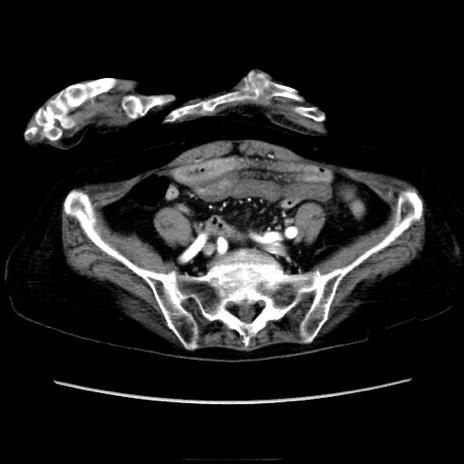

症例40(横断像)

【症例】90歳代女性

【主訴】腹痛・嘔吐

【現病歴】 食欲低下、嘔吐があり昨日他院受診。肺炎と診断され入院となる。入院後より腹部全体に圧痛あり。胃管留置され経過みていたが、症状持続するため、

当院転院となる。

【身体所見】腹部:中央に激痛あり、圧痛あり、反跳痛不明

【データ】WBC 17100、CRP 18.82

横断像